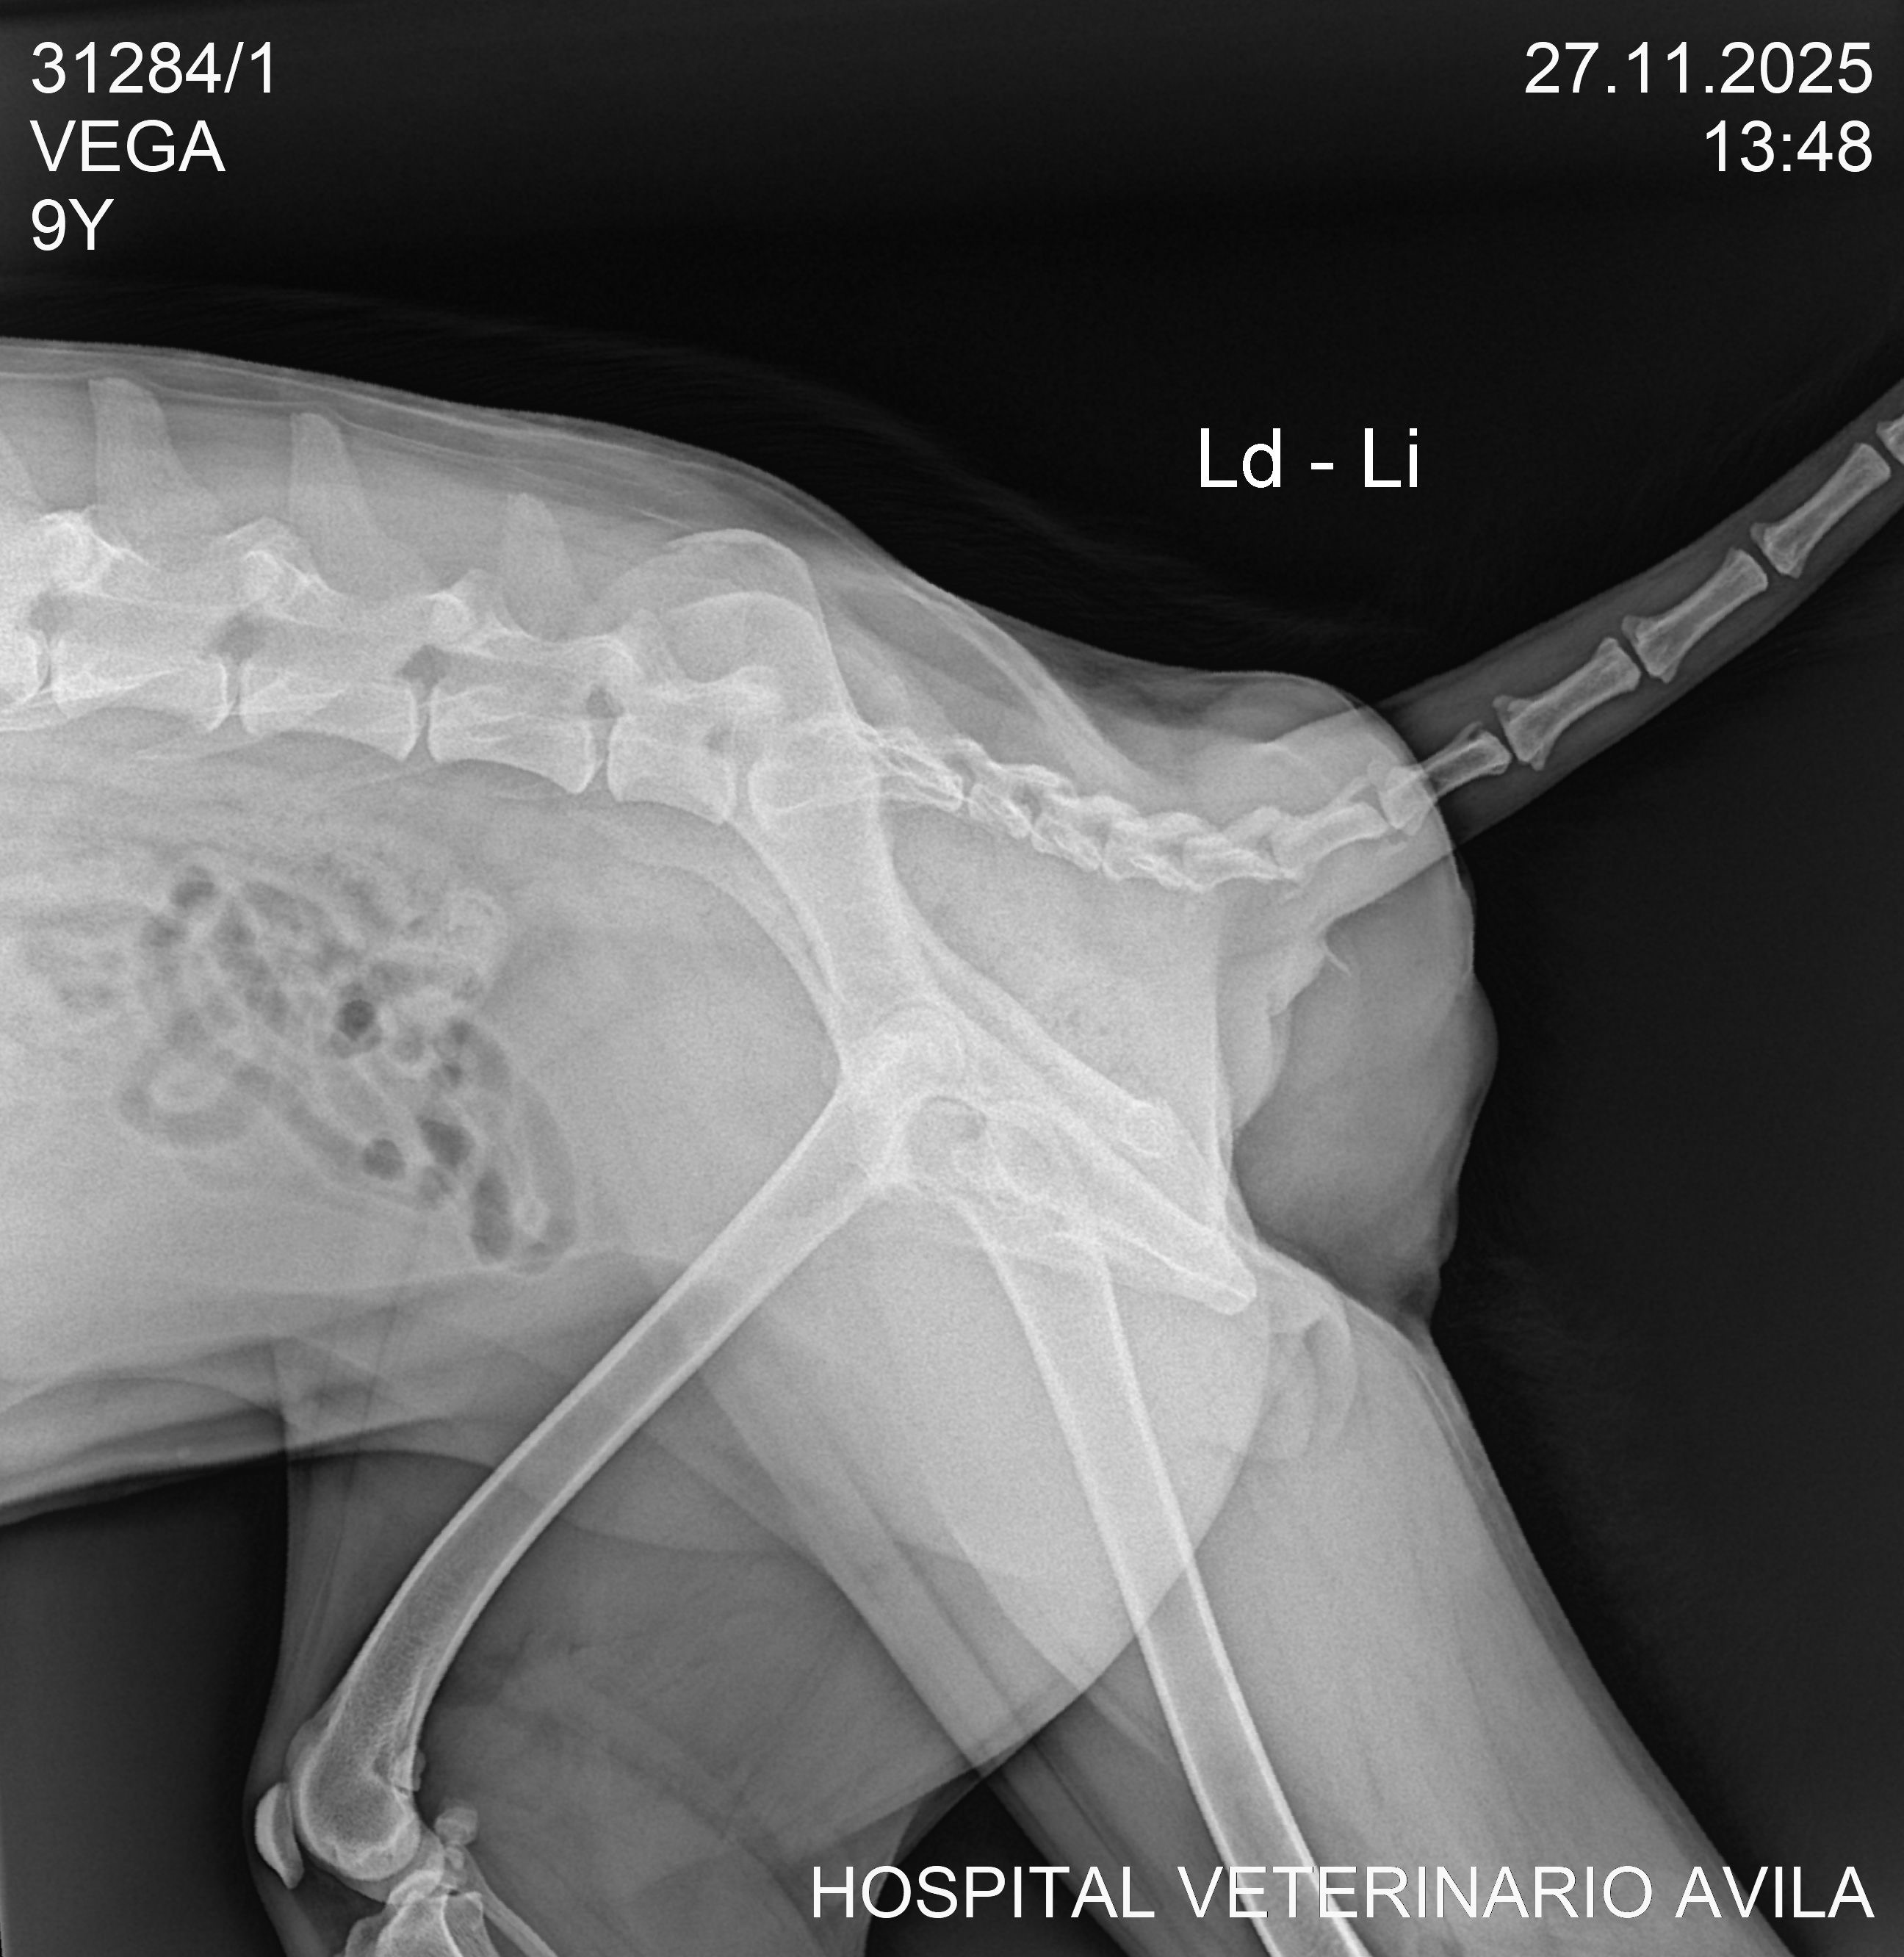

Vega has a cancerous tumor. Please help us raise funds for her surgery and electrotherapy so that we can give her a long life!

The surgery itself costs $500, plus the electrochemotherapy and follow-up medications. The veterinarian believes this treatment will work! We believe so too! Help us give her a fighting chance.